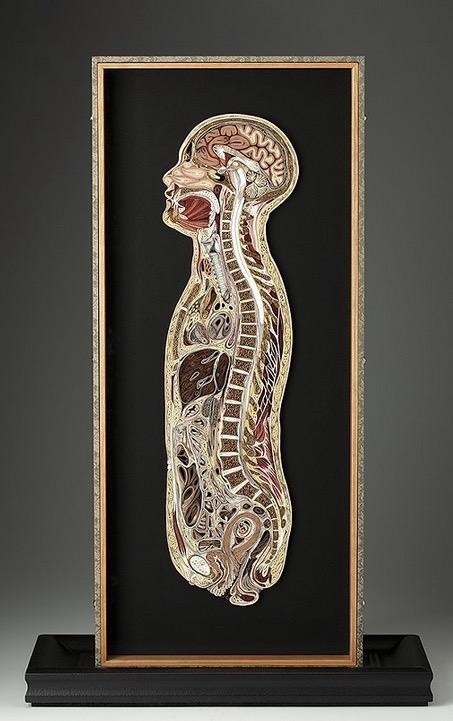

Nilsson'ın "Doku Serisi" adını verdiği çalışmasında insan ve hayvanlara ait beyin, kaslar, gövde ve birçok organın kesiti yer alıyor.